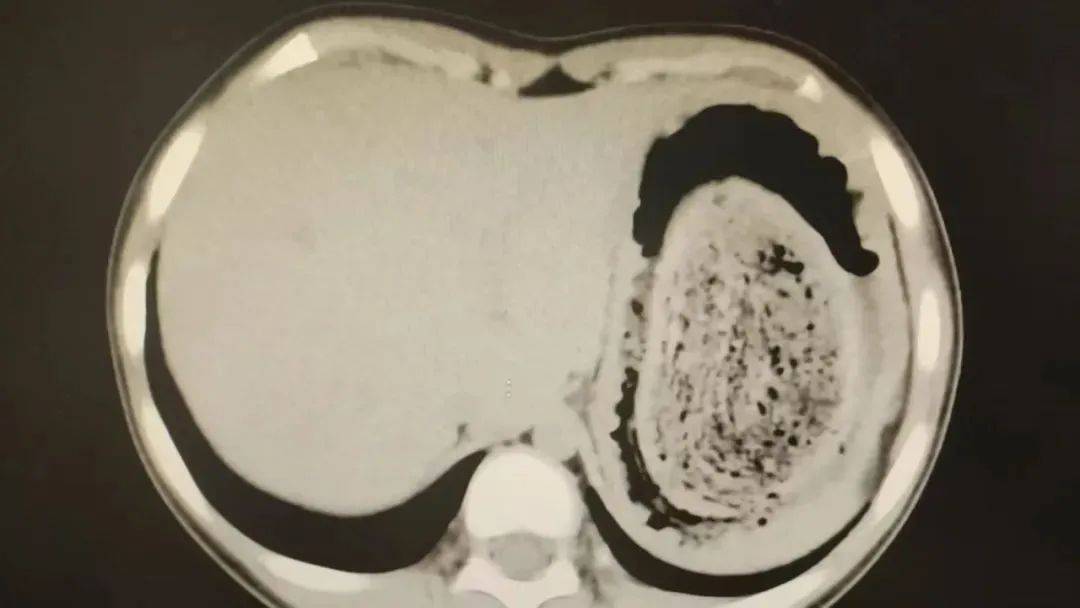

在胃镜帮助下,妮妮胃里的情况逐渐明了苏格兰超级联赛。一个滚圆黑色的毛发球混合着食物残渣占据整个胃腔,这些头发相互缠绕形成一个实心的“发石”,此外胃里还有一个鸡蛋大小的溃疡。

症结找到了,就是这个巨大的发石导致妮妮出现营养不良、贫血和闭经,当务之急就是取出“发石”,给胃进行“大扫除”苏格兰超级联赛。

“发石”混杂着食物残渣,就像一个黑色的小西瓜苏格兰超级联赛。由于整个“发石”体积太大,为避免损伤胃壁,医生借助手术工具将“发石”切割、分解,再小心翼翼地分块取出。整场手术持续2个多小时,最终取出4斤头发碎片。

10岁女孩园园(化名)因持续3天的上腹痛伴呕吐被紧急送医苏格兰超级联赛。影像学检查结果显示,她的胃部存在一个巨大的团块状阴影,初步怀疑为异物堵塞。据家长回忆,园园从1年前开始就有偷偷吃头发的习惯,但家人并未重视,直到这次症状严重才意识到问题的严重性。